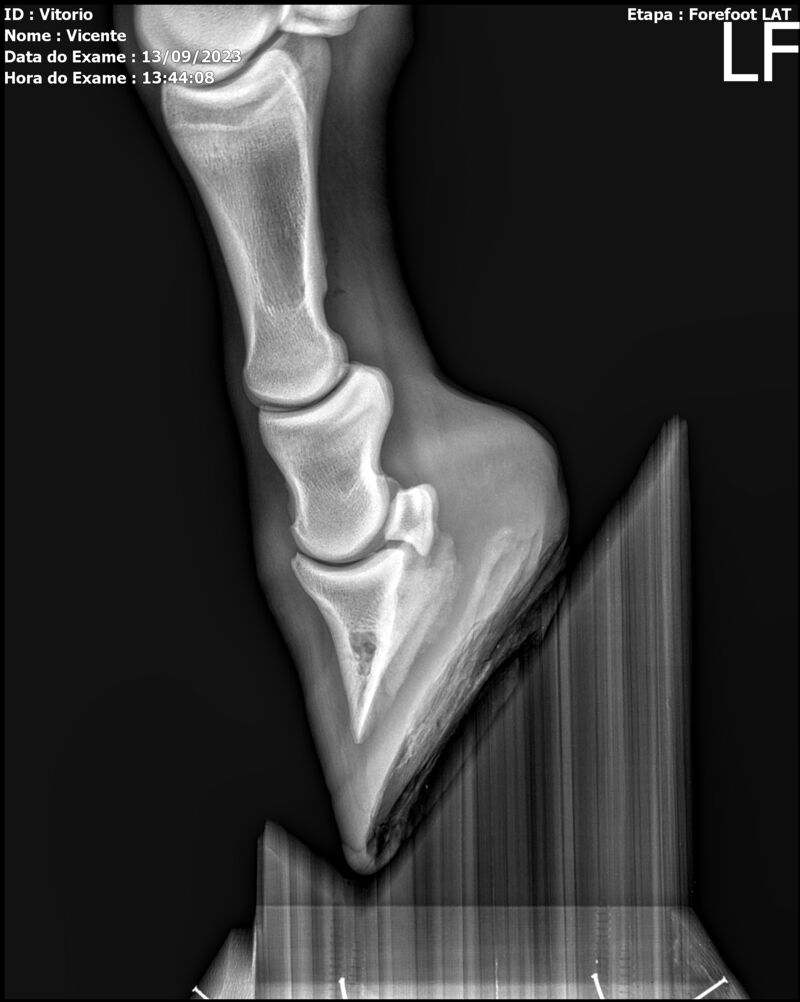

THUNDER ZC

Raça: BRASILEIRO DE HIPISMO

Sexo: MACHO - POTRO

Nascimento: 17/09/2022

Altura Aproximada: 1,54

Pel.: CASTANHO

Registro: EM AND

Vend.: VICENTE CONTE

Local : PORTO FELIZ/SP